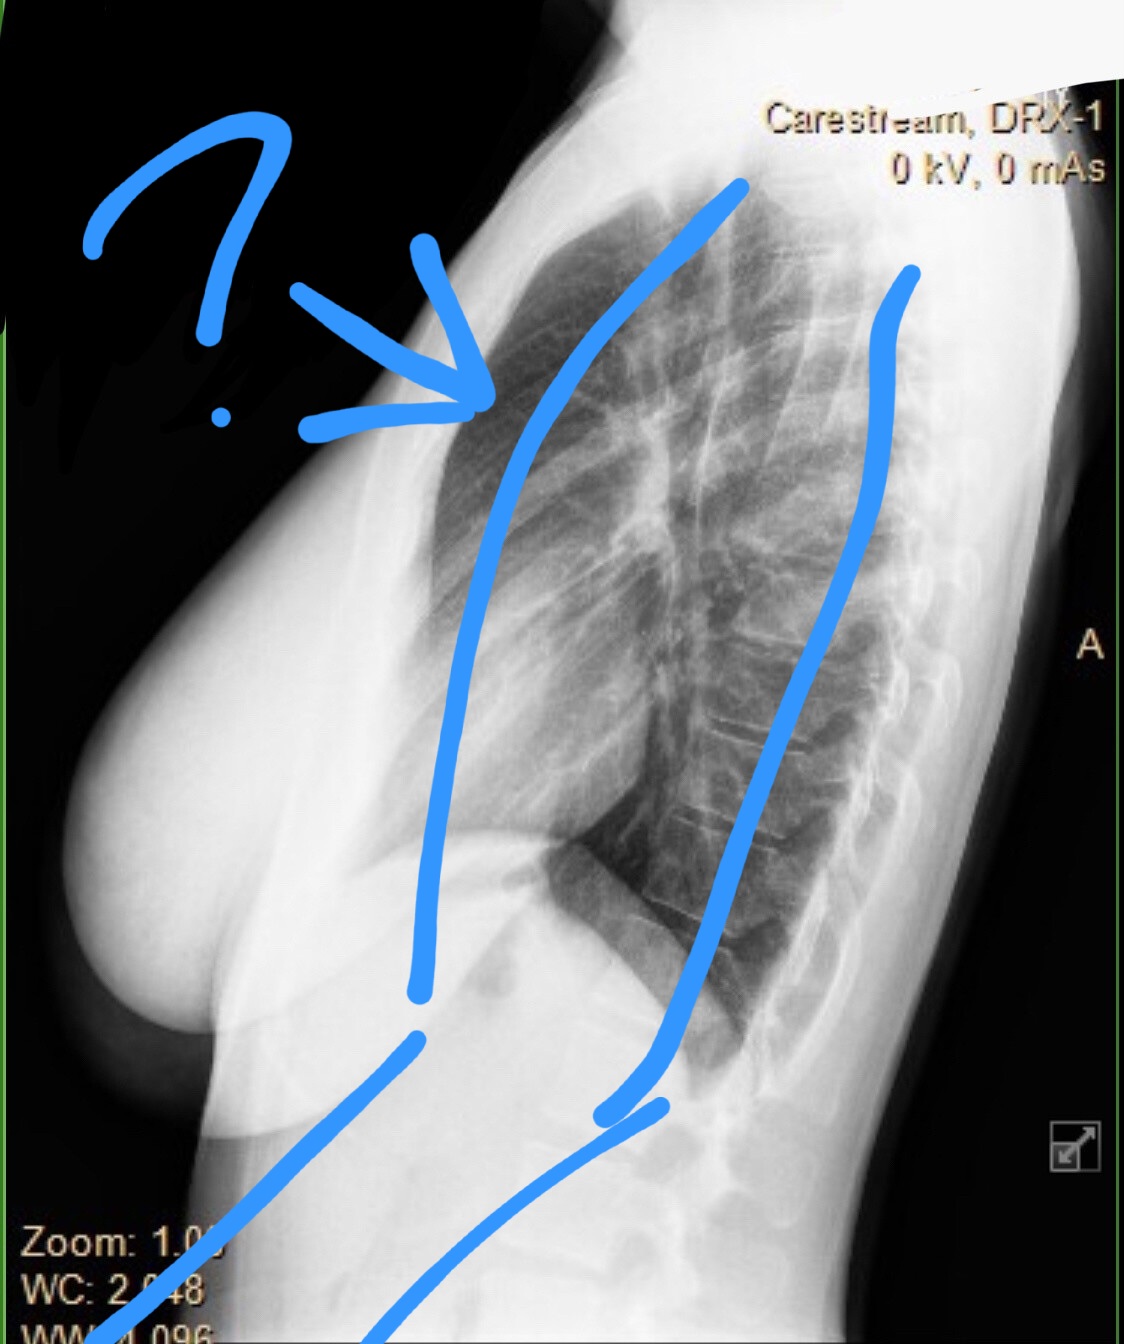

02/01/26(Sun)01:29:16 No.77050838 >warming up the snatch

>get to 60kg

>feel sharp pain in my upper back

>power through it for the rest of the day

>second day I can barely move

>get xrayed and see this

Is it fucking over for me? I’m an Olympic hopeful for 2028

Look at my c6. It’s not supposed to look like that

02/01/26(Sun)02:17:59 No.77050922 >>77050849

>hey coombrained internet retards, diagnose my spinal injury

02/01/26(Sun)06:07:16 No.77051322 >>77050849

C6... ah, you sunk my battleship.

02/01/26(Sun)06:50:41 No.77051384 >>77050849

that's your T6. your C6 is not present in this image. it could be spondylolisthesis, no one here knows doe

02/01/26(Sun)07:41:54 No.77051451 >>77050849

C is cervical, and I see fuckall at your D6. nice tits tho. Also that's a very underexposed xray

02/01/26(Sun)07:59:13 No.77051481 Bro an x ray won't show a slipped disc or anything because it's soft tissue damage

Get an MRI then get back to us

02/01/26(Sun)14:12:10 No.77052131 >>77050838

Looks like your scapula is sticking out, not your spine

If you follow the nubs on the back of spine bones, you're fine

I would bet you had a rib move since you could power through it

02/01/26(Sun)15:25:56 No.77052256 Is this what you're tripping over? Idk, it dosent look good, maybe a slipped disc.

Your only hope now is get a real strong back to compensate.

02/01/26(Sun)22:58:15 No.77053490 >>77052406

spondylolisthesis get a MRI

no, it's not over

it's only over when you stop trying to adapt and overcome this obstacle

i herniated one of my lower vertebrae on one side doing low-weight deadlifts

you'll be fine, just give the surrounding musculature time to compensate. I was able to fully load my lifts that had targets localized to that area within a few months, but it took doing nothing but laying in bed unfortunately for a few weeks. might be a similar situation for you of laying off doing shit

give it time

WAGMI bbg